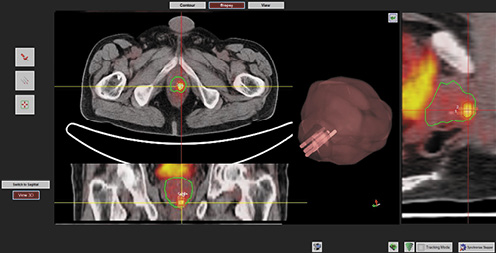

The Bio-Jet fusion system and software (D&K Technologies, Barum, Germany) will be used. The prostate profile and ROIs will be drawn on PSMA PET/CT and mpMRI and fused in real time with the TRUS image stack during biopsy. Biopsies, transrectal or transperineal according to lesion site, will be performed with patients in the dorsal lithotomy position, under antibiotic prophylaxis and local anesthesia, using 3D triplane transrectal ultrasound system (BK Medical, Analogic Ultrasound Group, Pro Focus, Transducer 8818, 6/9 MHz). Biopsy cores will be numbered according to ROI number and topography. Specimens will be processed and evaluated by a genitourinary pathologist. Tumor foci will be quantified and graded according to the ISUP consensus conference on Gleason grading (Fig. 1).

Software fusion biopsy of the ROI delineating the lesion positive at 68Ga-PSMA PET/CT; the green line delineates the prostate gland and the red line the contoured target lesion. The number of cores and their corresponding tumor sampling are defined in the three-dimensional volume-rendering panel.